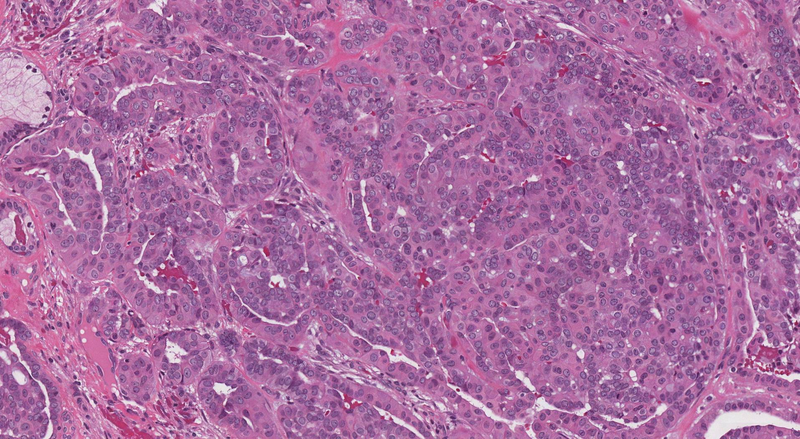

Đa số các trường hợp ung thư đại trực tràng là ung thư biểu mô tuyến, chúng bắt đầu từ các tế bào biểu mô. Khoảng 71% ung thư đại trực tràng mới xuất hiện ở đại tràng và 29% xuất hiện ở trực tràng. Các loại khối u ác tính ít phổ biến hơn gồm có khối u carcinoid, khối u tế bào stroma đường tiêu hóa và u lympho. Yếu tố nguy cơ lớn nhất đối với ung thư biểu mô tuyến đại trực tràng đơn phát là tuổi cao, với 99% trường hợp xảy ra ở người từ 40 tuổi trở lên.